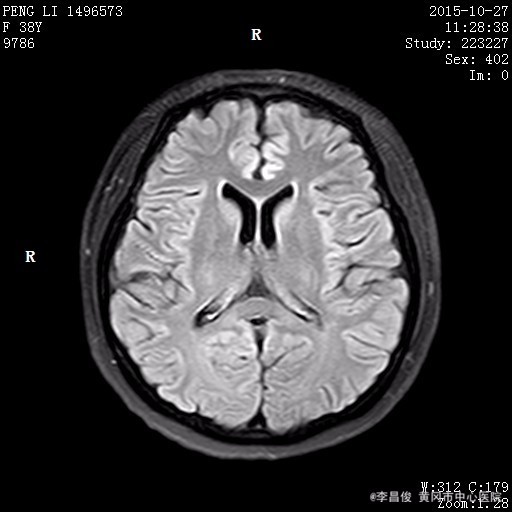

体格检查:BP130/90mmHg、 HR90次/分、 R16次/分, T36.5℃ 神清,精神欠佳,步入病房,查体合作。全身皮肤巩膜无明显黄染,结膜充血,全身多处淤青。颈软,甲状腺未及,双肺呼吸音清,未闻及明显干湿啰音,心律齐,各瓣膜区未闻及明显病理性杂音,腹软,肝脾肋下未及,双下肢不肿。 专科情况:神清,双侧瞳孔等大等圆,对光反射灵敏,四肢肌力肌张力正常,双侧病理征阴性,四肢有震颤。 辅助检查结果: 2015.10.25 头部CT:脑萎缩,建议结合临床必要时行MRI检查。2015.10.27 头部MRI:1.脑白质疏松;2.小脑萎缩;3.筛窦炎。 2015.10.26 血常规:白细胞 9.08*10^9/L,红细胞 3.47*10^12/L,血红蛋白 132g/L,血小板 88*10^9/L,中性粒细胞比率 92.2%;肝肾功能血糖血脂电解质:谷丙转氨酶 65.1U/L,谷草转氨酶 139.4U/L,尿酸 644.2umol/L,葡萄糖 8.16mmol/L,总胆固醇 9.93mmol/L,高密度脂蛋白胆固醇 3.87mmol/L,低密度脂蛋白胆固醇 4.86mmol/L,同型半胱氨酸 58.21umol/l;肌肉酶谱:磷酸肌酸激酶 309.1U/L,乳酸脱氢酶 397U/L;